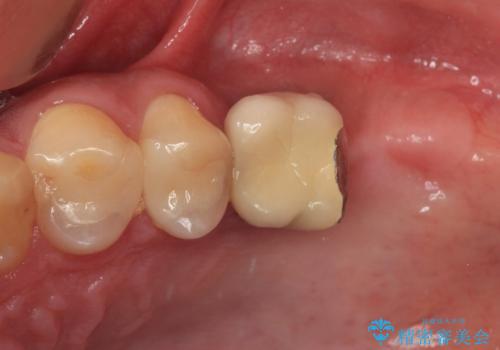

- 黄ばんだ前歯や目立つ奥歯の銀歯をきれいにしたいとのことで来院された患者様です。

小さい修復物の銀歯が装着されている歯はセラミックインレーにて、その他はオールセラミッククラウンにて補綴治療を進めることとしました。